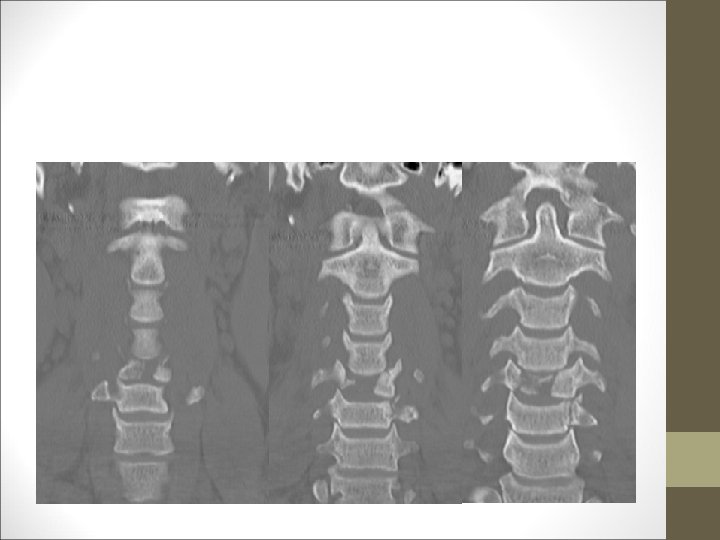

TC Desplazamientos de fragmentos óseos ¿Algo mas? Desplazamientos discales y lesiones ligamentosa FACULTAD DE MEDICINA DEPARTAMENTO DE CIRUGÍA NEUROCIRUGÍA RM